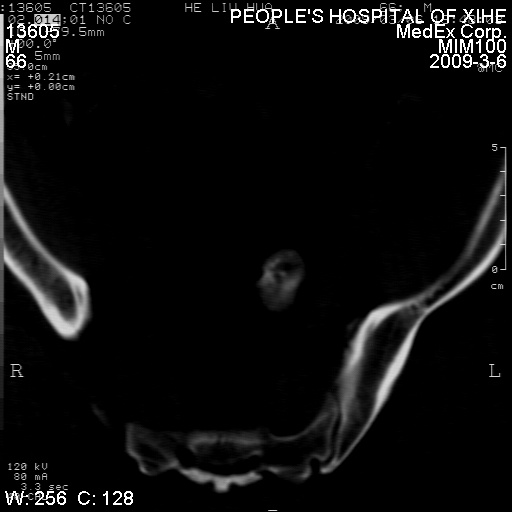

标题: CT18522:男,66岁。考虑结核有错吗 [打印本页]

标题: CT18522:男,66岁。考虑结核有错吗

x线片示:骶骨密度增高。